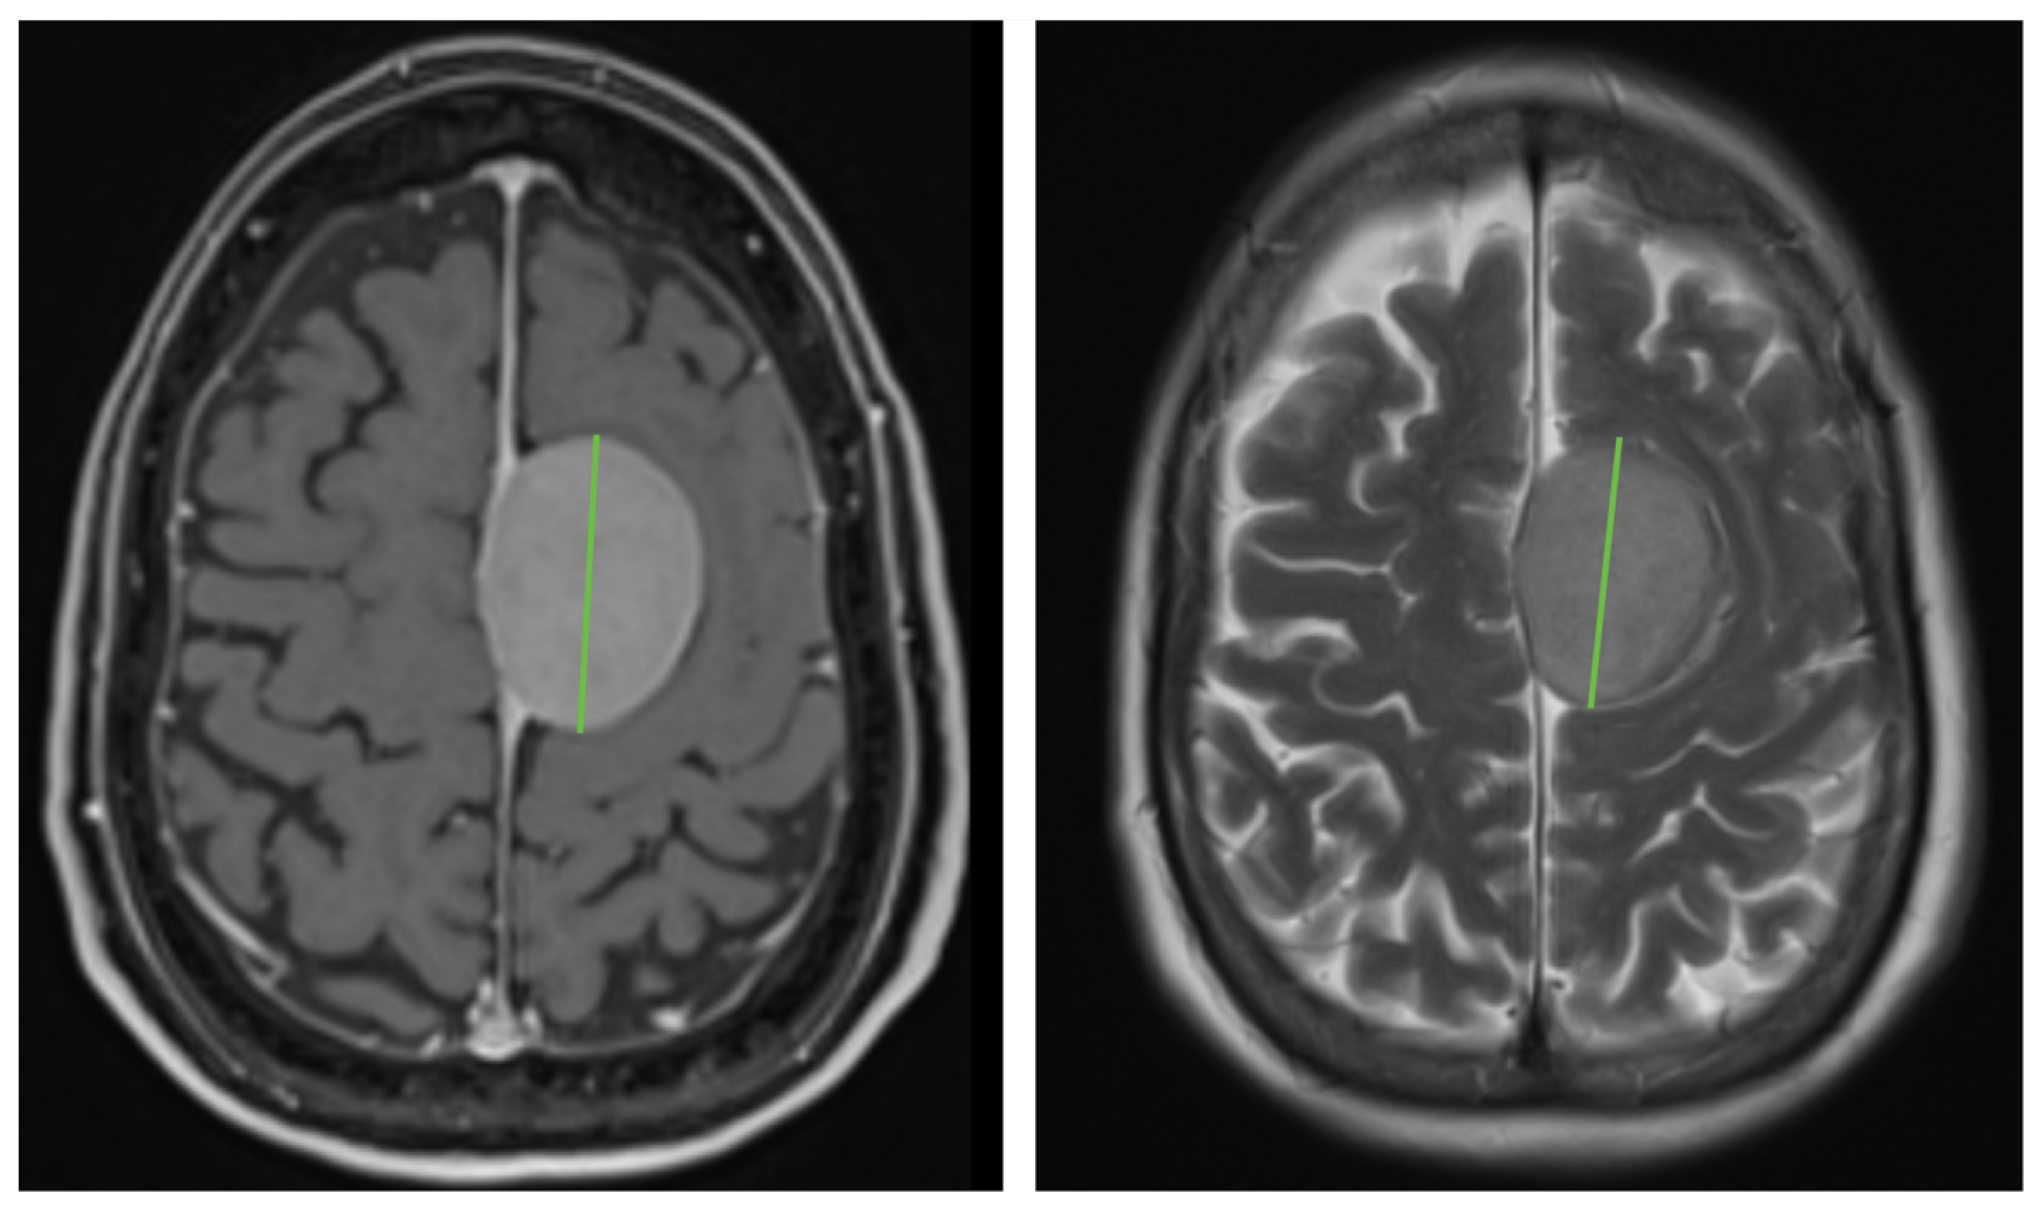

The MR images were evaluated by a well-instructed researcher and an experienced neuro-radiologist in consensus. The tumor size was defined by the maximum tumor diameter in the transverse plane on both the initial and follow-up CE-T1WI and T2WI (Figure 1). As most imaging sequences were scanned in the axial plane and not in 3D mode, tumor growth was calculated in millimeters by subtracting the initial tumor diameter from the final tumor diameter measured on the first and the follow-up CE-T1WI and T2WI images. In order to correct for follow-up time, tumor growth was recalculated to growth percentage per year.

Figure 1. Representative example of the method of measuring meningioma size in the transverse plane of a parasagittal meningioma with a maximum diameter of 45 mm (green line) on CE-T1WI (left) and T2WI (right).